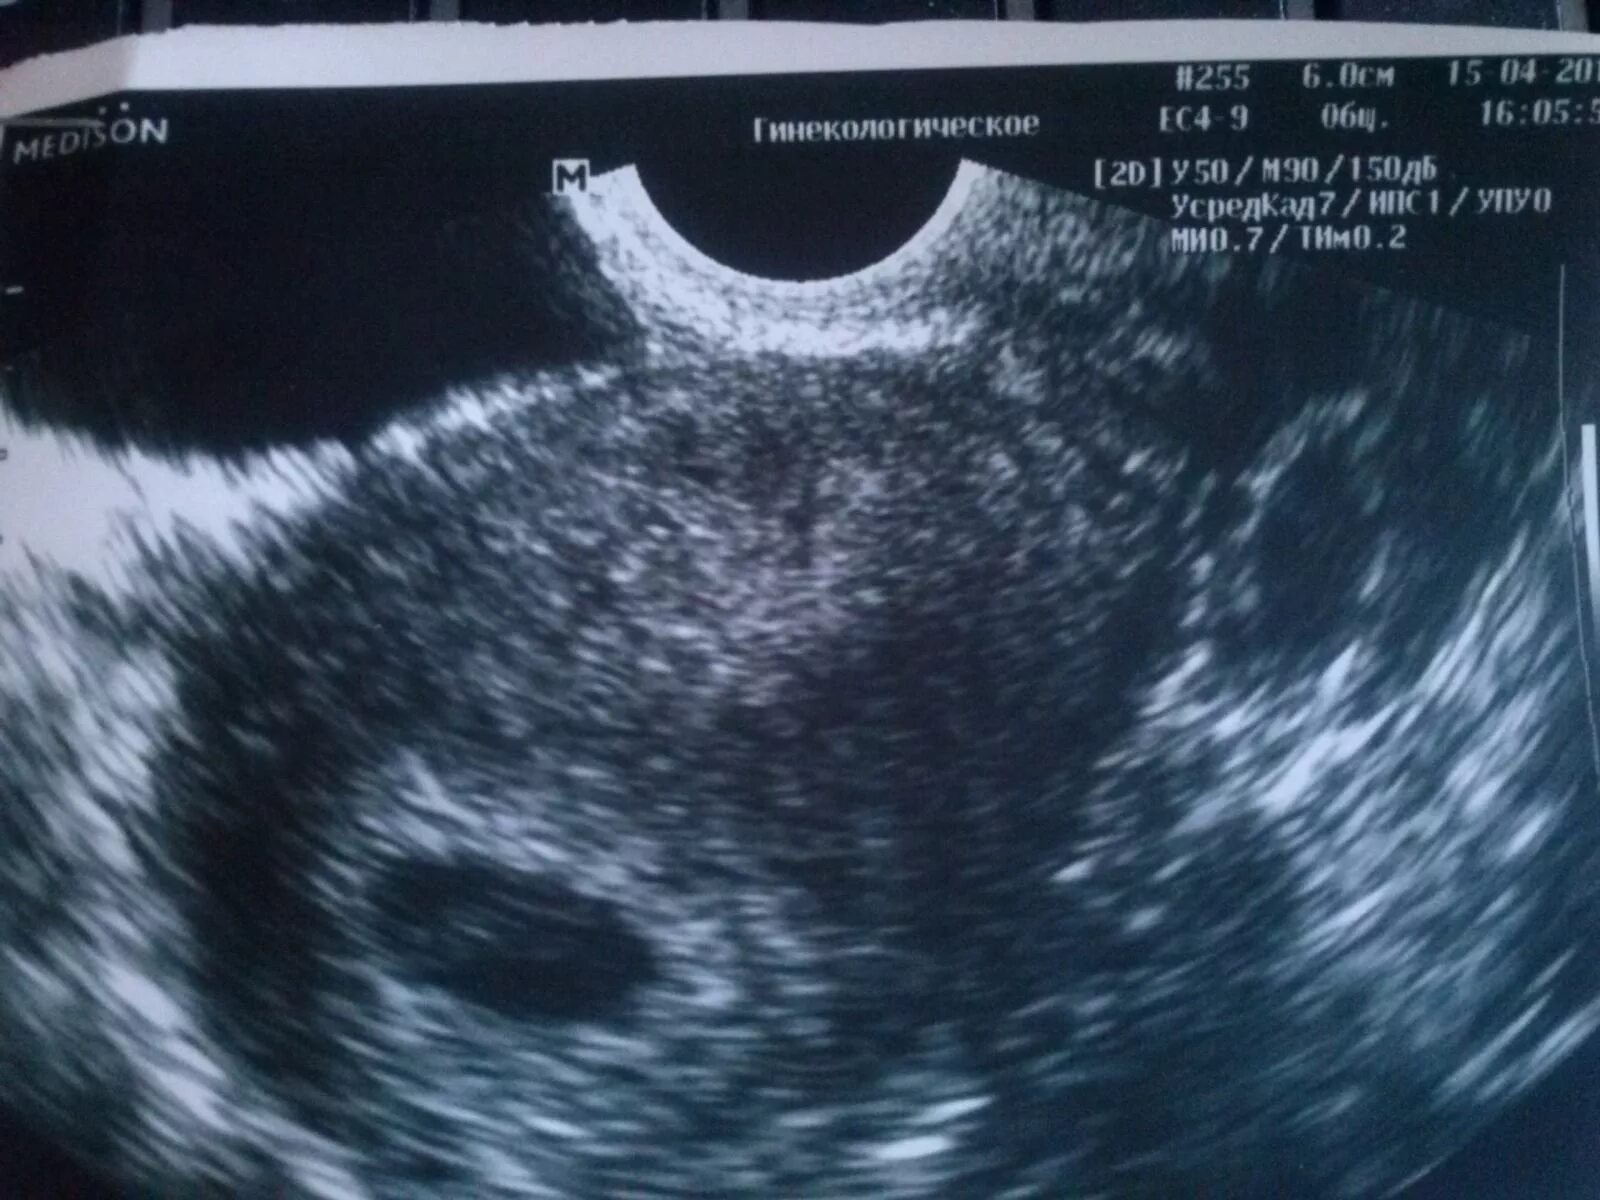

Плодное яйцо 3 мм